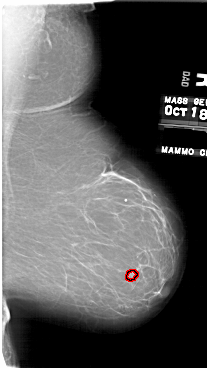

A_1748_1.LEFT_MLO

LEFT_MLO LINES 6361 PIXELS_PER_LINE 3736 BITS_PER_PIXEL 12 RESOLUTION 43.5 NON_OVERLAY

FILE: A_1748_1.RIGHT_MLO.OVERLAY

TOTAL_ABNORMALITIES 1

ABNORMALITY 1

LESION_TYPE MASS SHAPE LOBULATED MARGINS CIRCUMSCRIBED

ASSESSMENT 3

SUBTLETY 3

PATHOLOGY BENIGN

TOTAL_OUTLINES 1

BOUNDARY